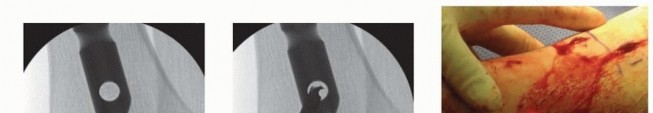

### TECH FIG 9 • A. A drill bit is used to ensure the guidewire is placed centrally in the distal segment of this distal metadiaphyseal fracture. B,C. The nail length guide is pushed to the opening of the tibia and verified with lateral fluoroscopic imaging. Device manufacturers supply nails in variable increments. When a length measurement falls in between lengths, choose the shorter length. A threaded end cap (usually 5, 10, and 15 mm) can be used if it is desired to bring the nail to top of the canal opening. Leaving the nail countersunk below the bone surface does not compromise stability in middle and distal fractures but may complicate future nail extraction. 558 Reaming the Canal Before reaming, estimate the narrowest canal diameter using both AP and lateral plain radiographs. Alternatively, intramedullary reamer sets typically have a radiolucent ruler that allows for intraoperative fluoroscopic verification, which should be done on both the AP and lateral views. The canal typically is reamed at least 1 mm over the isthmic diameter to minimize the risk of nail incarceration. Reaming should begin with an end-cutting reamer—the 8.5- or 9-mm size in most systems. Reamer heads should be evaluated before insertion and should be sharp and free of defects. Insert the reamer head into the proximal metaphysis with the knee in maximal flexion before applying power to avoid distorting the entrance hole ( TECH FIG 10A). Reamers are advanced at a slow pace under full power. If the reamer shafts are not solid, but are wound, be sure to avoid using reverse when drilling because that would cause the reamers to unwind if resistance is encountered within the intramedullary canal. Care must be taken not to inadvertently extract the guidewire when the reamers are removed. Multiple techniques are used. First, manual downward pressure can be applied to the wire with specialized instruments, medicine cups, or cleaning cannulas ( TECH FIG 10B). Once the reamer has cleared the opening, it can be clamped and held in position ( TECH FIG 10C). For the minimally reamed technique, a single end-cutting reamer (usually 9 mm) is passed down the canal to ensure the smallest diameter nail can pass through the narrowest segment of the intramedullary canal. In an effort to minimize thermal damage to the endosteal cortex, reaming should be discontinued within 0.5 to 1 mm of hearing the reamer head catching (“chatter”) on the endosteal cortex. Care also should be used when there are butterfly or oblique fracture fragments. Continued reaming after encountering chatter may result in iatrogenic comminution and loss of reduction.

### TECH FIG 10 • A. Maintenance of maximal knee flexion protects the entrance hole from being inadvertently enlarged by the reamer. B. If the guidewire is rotating during reaming, it must be held down as the reamer is pulled back to avoid inadvertent removal of the guidewire. C. A clamp can be used to grasp the guidewire when the reamer head clears the soft tissues. Unreamed Technique Standard preparation technique is used for the starting hole, and the fracture is reduced. Precise evaluation of the lateral isthmic diameter is repeated, and a small-diameter nail is selected, typically in the 7- to 9-mm range. A good guideline is to use a nail 1 to 1.5 mm smaller than the narrowest measure of the isthmus on the lateral radiograph. If lateral plane imaging is suggestive of canal diameter very close to nail size, a single pass with an end-cutting reamer usually is performed to decrease the possibility of nail incarceration. The nail is inserted and impacted in standard fashion. If significant resistance is encountered when the nail reaches the isthmus, the nail is removed to avoid incarceration or iatrogenic fracture propagation. A reamer 0.5 to 1.0 mm larger than the nail is passed down the canal, and nail passage is attempted again. Nail Insertion Once the nail insertion handle is attached, pass a drill through the proximal screw insertion attachment and screw insertion cannulas before inserting the nail to ensure accurate alignment of the attachment jig. Maintain nail rotation during insertion by aligning the center of the insertion handle with the tibial crest. Consider internal rotation of the nail if distal AP interlocking bolts are deemed necessary to minimize damage to distal neurovascular structures. Maintain knee hyperflexion during nail insertion to minimize the risk of posterior cortical abutment and iatrogenic fracture. Impact the nail to the final depth using lateral plane fluoroscopy. Interlocking Bolt Insertion In simple transverse fractures, place distal interlocks first to allow for backslapping for interfragmentary compression and gap minimization. Usually, distal interlock bolts are placed medial to lateral. Position the leg in slight extension and stable neutral rotation. 559 Rotate the C-arm to lateral imaging position and pull the tube back away from the medial side of the leg to allow for drill placement. Rotate the leg and C-arm individually and sequentially to create a perfect circle image; optimize this view before drilling attempts ( TECH FIG 11A). After localizing the interlocking hole using a clamp and fluoroscopy, make an incision large enough to place the locking bolt. Use blunt clamp dissection until the cortex is reached. Use a sharp drill point and place the center of the point in the center of the circle. Hold the drill obliquely to the nail axis to simplify repositioning ( TECH FIG 11B). Once the central location is achieved; align hand and drill with imaging axis. Fluoroscopes with laser alignment guides can be helpful to assist with alignment by centering the laser on the skin incision and then placing the laser in the center of the back of the drill when preparing to drill the hole ( TECH FIG 11C). Drill to the midsagittal point in the tibia. Then, disengage the drill from the drill bit and check the fluoroscopic image. If the drill is accurately positioned in the center of the hole, advance the drill bit with power through the far cortex; avoid broaching the far cortex by impacting with a mallet to avoid iatrogenic fracture. Drill the second interlock hole using the same technique but maintaining a parallel axis with the first successful drill passage. Replace the drill with the appropriate depth gauge and check an AP image before screw length selection. Once interlock lengths and position are verified, “backslapping” can occur to optimize compression. Using the slotted mallet attachment on the insertion handle, superiorly directed mallet blows can be used while pressure is applied to the foot in order to compress the fracture site. Fluoroscopy should be used to monitor the amount of compression and the nail position proximally. If backslapping is planned, the nail should be slightly overinserted to avoid nail prominence after compression is performed.